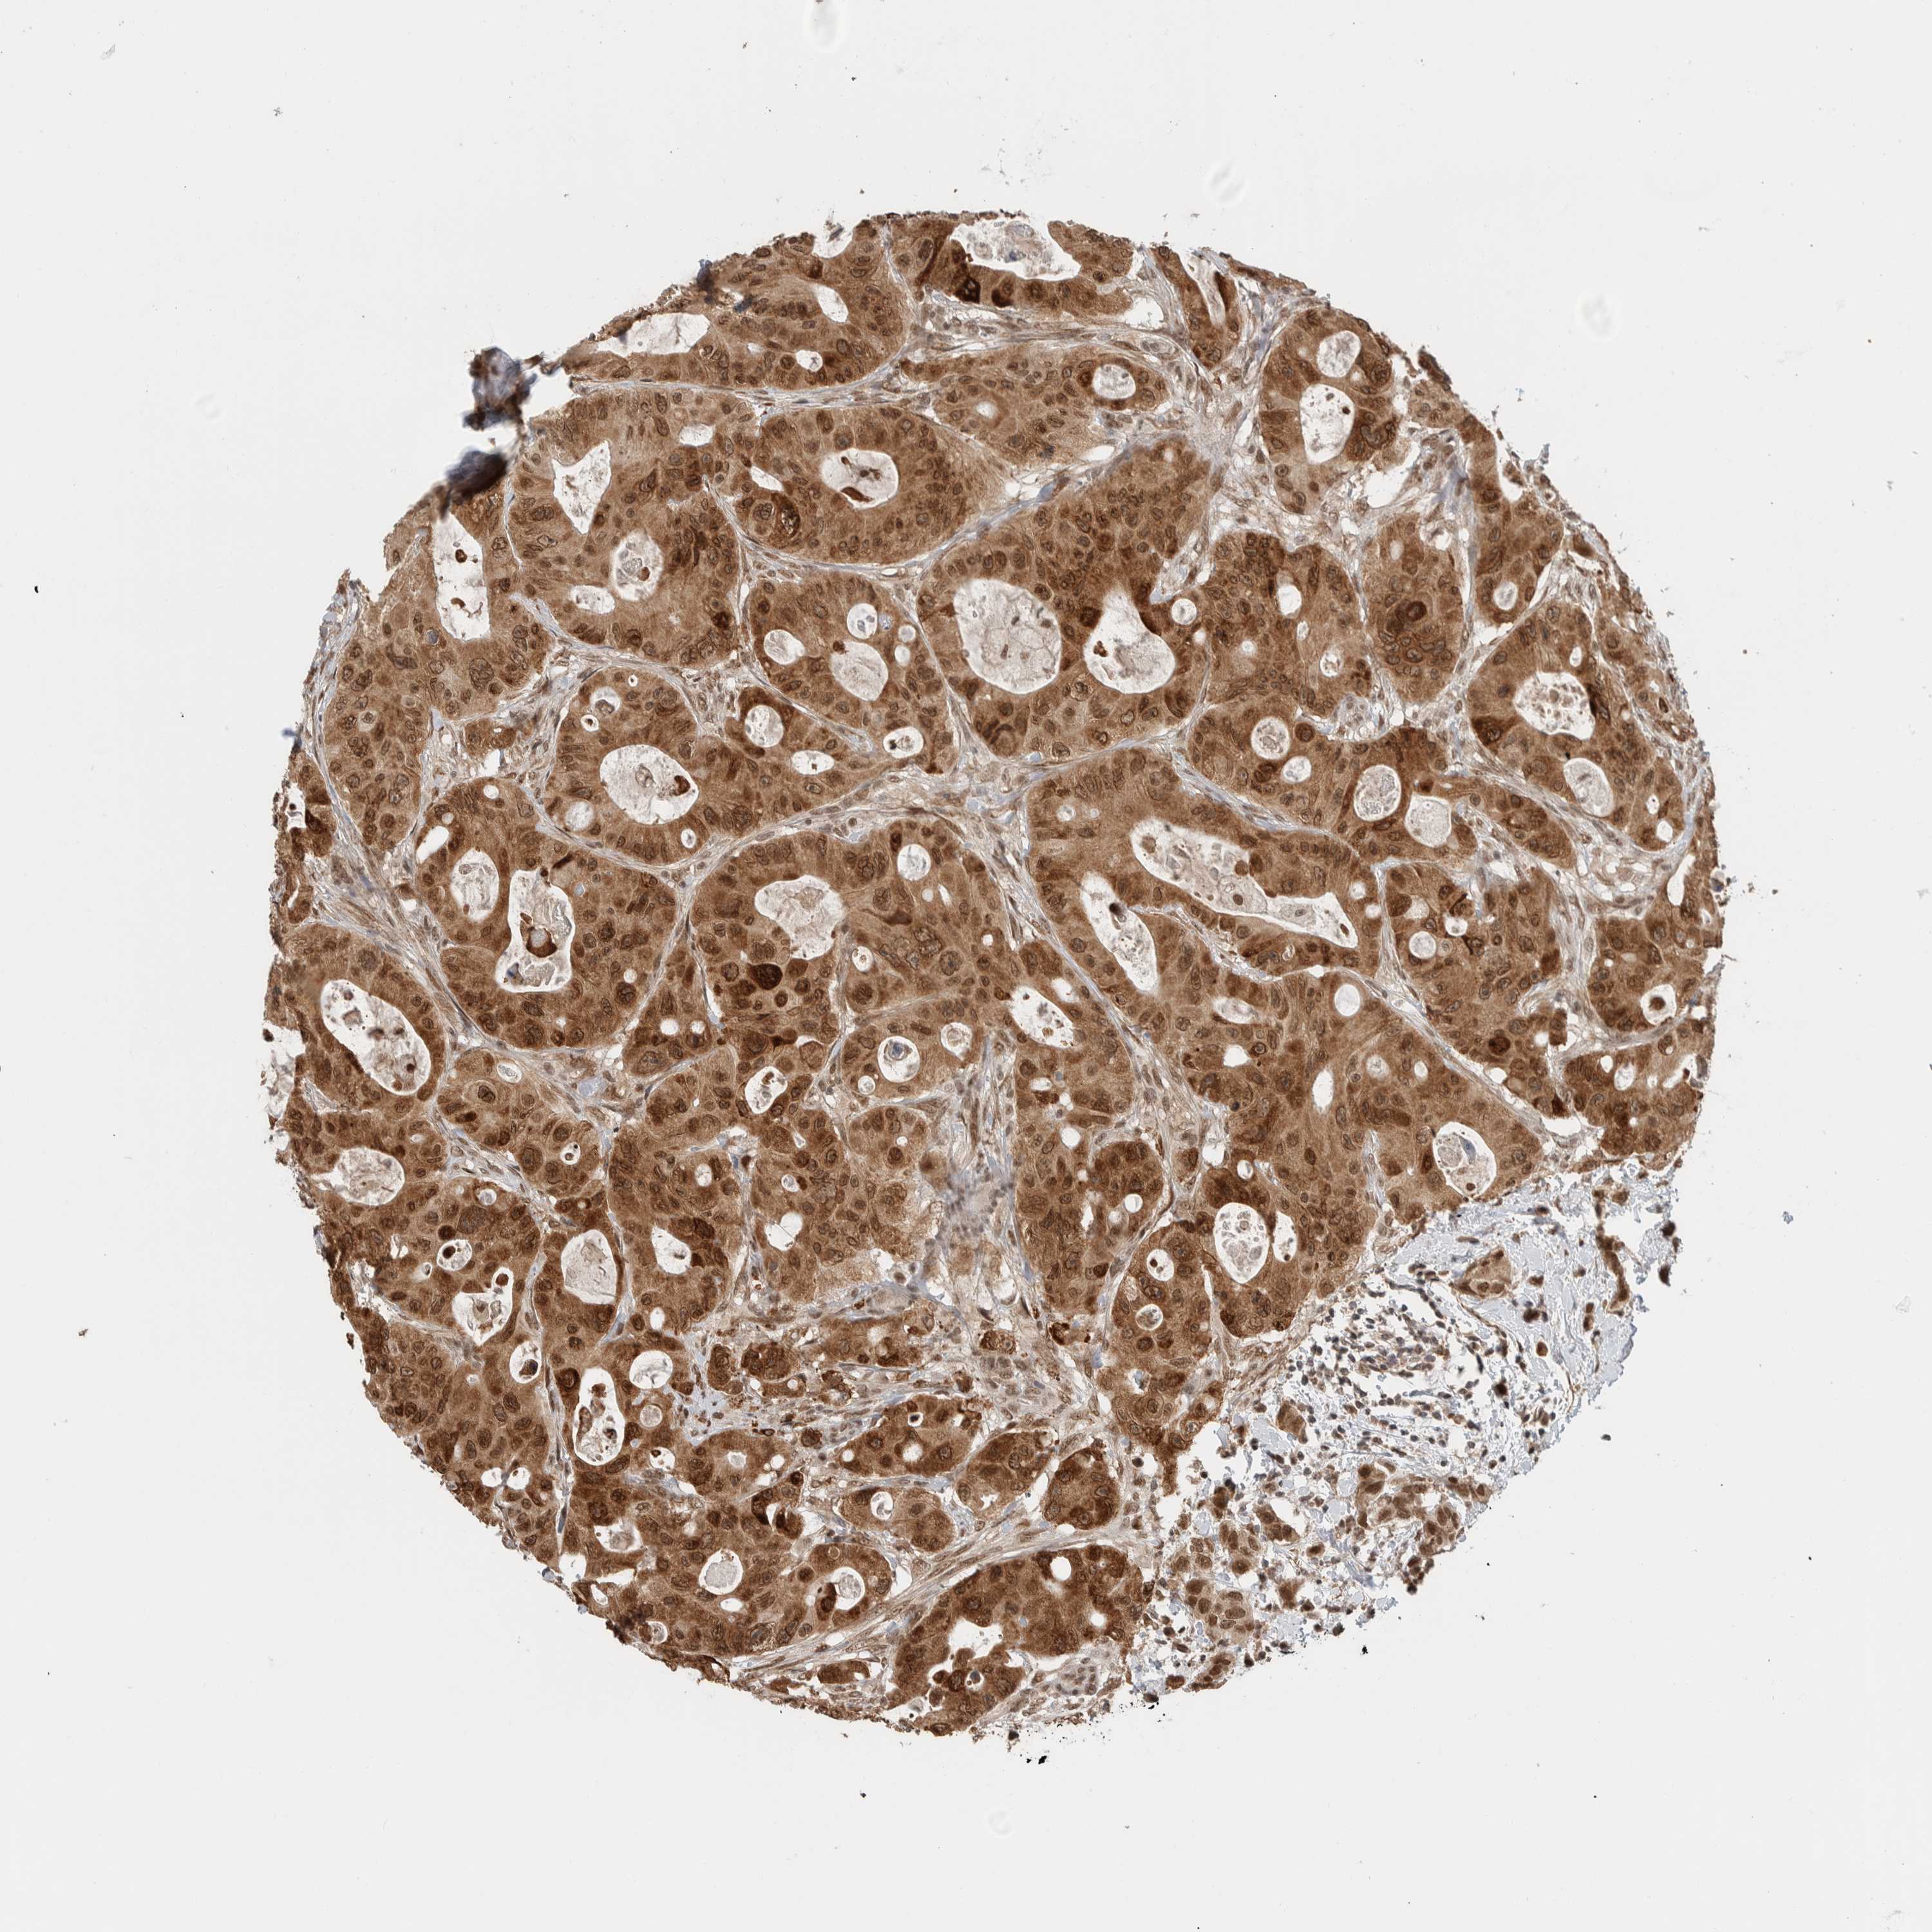

CANCER COLORECTAL CANCER Show tissue menu

Colorectal cancer

Colon adenocarcinoma